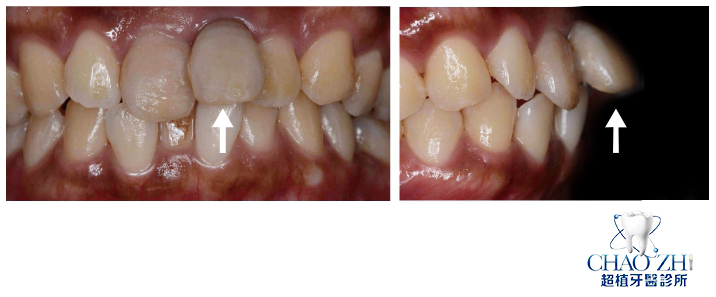

經過醫師簡單洗牙以及護士用心教導我正確的刷牙方式後,我陸續進行了齒模咬合建膜的前置動作,為了之後利用3D模組配合齒模做出牙套,自己的嘴巴算是首次被口腔固定器完全撐到最大,另外護士還手持相機進行齒顎矯正前取模口腔拍攝,讓我久違找回過去愛笑時期所歷經的嘴痠過程,但也同時令我真正面對自己一口亂牙的事實,像極了市中心凌亂的機車停放情況。

在最後進行X光拍攝後,牙套建膜的前置流程也正式進入尾聲,諮詢護士為了提供更私密的矯正諮詢,特別在諮詢室內將各個不同類型牙套矯正方式向我做了仔細說明,而現在有不少人礙於外表,都會選擇隱形牙套來做牙齒矯正,這一點即使是我妹也是一樣。